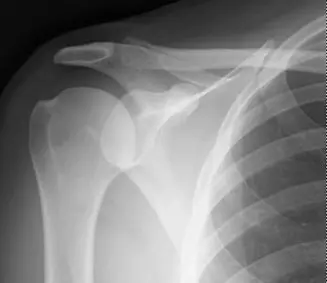

التصوير الشعاعي (الأشعة السينية)

بعد رد الكتف إلى مكانه، تُجرى الأشعة السينية لتقييم العظام. على الرغم من أنها قد لا تظهر جميع التفاصيل، إلا أنها حاسمة في:

• تأكيد رد الخلع: التأكد من أن رأس العضد عاد إلى مكانه الصحيح.

• الكشف عن كسور العظام الكبيرة: يمكن أن تكشف عن كسر بانكارت العظمي الكبير (شظية عظمية من الجوف الحقاني) أو إصابة هيل ساكس (انخفاض في رأس العضد).

وصف طبي دقيق للمريض

شكل 1: صورة أشعة سينية محورية بعد رد الخلع توضح إصابة بانكارت العظمية (سهم) وإصابة هيل ساكس (رأس سهم).